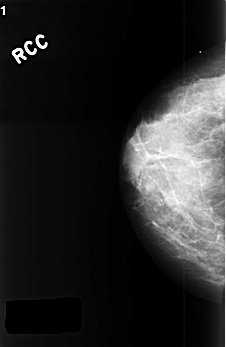

C_0393_1.RIGHT_CC

RIGHT_CC LINES 4504 PIXELS_PER_LINE 2936 BITS_PER_PIXEL 12 RESOLUTION 50 NON_OVERLAY